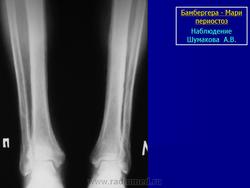

Рентгенологически Бамбергера - Мари периостоз проявляется утолщением диафизов симметричных костей за счет периостальных наслоений, которые выглядят ровными, гладкими, менее плотными, чем кортикальный слой диафизов. В дальнейшем периостальные наслоения могут приобретать плотность кортикального слоя и сливаться с ним. Типичны симметричность поражения и перестройка кортикального слоя в виде его продольной исчерченности.

Анатомическая и рентгенологическая картина системного оссифицирующего периостоза выражается в системном симметричном поражении преимущественно длинных трубчатых периферических костей (рис. 313). Больше всего изменены диафизы, отчасти также и метафизы костей предплечья и голени, пястных и плюсневых костей, а также основных и, средних фаланг. Эпифизы, лишенные надкостницы, остаются пощаженными. Важно, что оссифицирующую реакцию проявляет только надкостница, но не эндост, костномозговой канал трубчатой кости при этой болезни не суживается (рис. 314).

Надкостничные наслоения окутывают кости обыкновенно со всех сторон в виде футляра и имеют очень гладкую или местами несколько слегка шероховатую поверхность (рис. 316). Иногда видна продольная .слоистость надкостничных остеофитов. Нередко раньше и больше всего вовлекаются в процесс дистальные концы диафизов. У взрослого обычно окостеневает лишь самая наружная, поверхностная часть надкостничных наслоений, так что на рентгенограммах между корковым компактным веществом диафиза и узенькой плотной полоской оссифицированной надкостницы остается светлая продольная полоса (рис. 317). Новообразованная костная ткань вначале отличается по своей структуре от плотного основного вещества и на вскрытии даже сравнительно легко отделяется от поверхности диафиза. Но в дальнейшем, через месяцы у детей и через годы у взрослых, она сливается в единую костную массу. Толщина надкостничных разрастаний равна от 1 до 7 мм. Необходимо иметь в виду, что хронический пролиферативный процесс гистологически сопровождается резким утолщением обоих слоев надкостницы и чрезвычайным богатством сосудов; мы здесь наблюдали при диагностическом проколе кости и при биопсии очень сильные кровотечения. Структурный рисунок самой кости не представляет никаких уклонений от нормы. Эпифизар-ные линии остаются всегда неизмененными. Истинная генерализация, т. е. поражение всего скелета, включая обычно остающиеся пощаженными кости черепа, позвоночника, ключицы, губчатые кости запястья и лредшшсны, здесь крайне редкое явление.